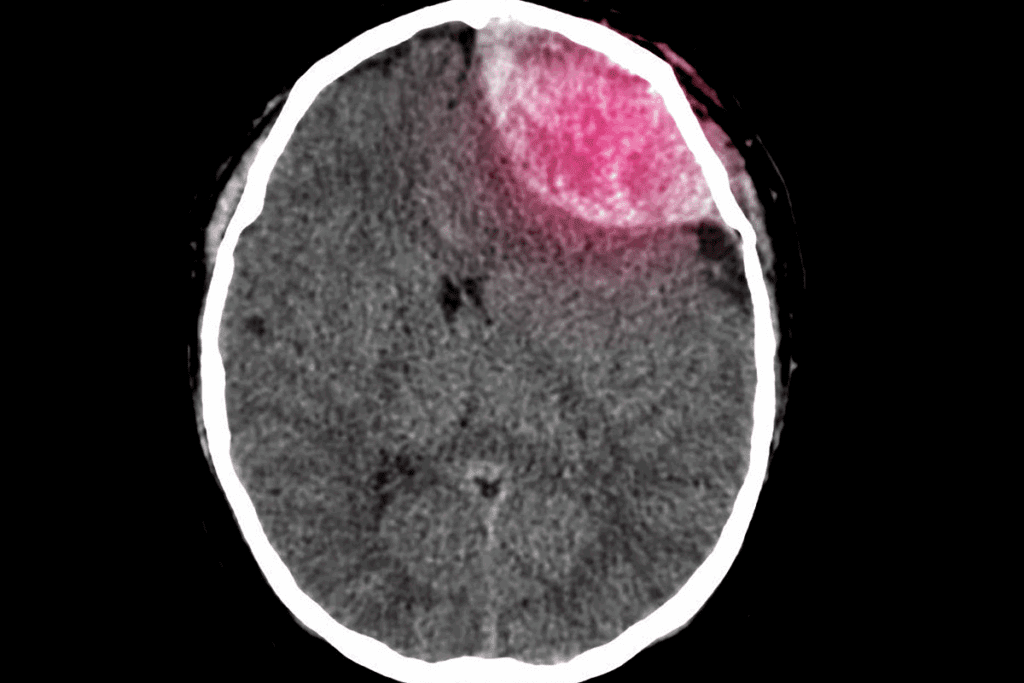

• Craniectomy: a surgery where a part of the skull is removed to relieve pressure on the brain.

A craniotomy removes a part of the skull temporarily. This is done to relieve brain pressure, remove tumors, or fix blood vessel problems. After surgery, the bone flap is put back, and the skull is fixed with plates or screws.

Craniectomy: Extended Skull Removal

A craniectomy removes a part of the skull that’s not put back right away. It’s used to reduce brain swelling or let the brain grow without skull limits. The removed bone might be frozen or stored under the skin for later use.